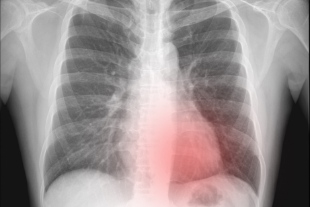

Mengungkap Ketangguhan di Balik Panggung, Kisah Idol Kpop Melawan Pneumothorax

Dunia K-Pop dikenal dengan gemerlap panggung, koreografi yang memukau, dan jadwal yang padat. Namun, dibalik sorotan lampu dan sorak sorai penggemar, para idol menghadapi tantangan kesehatan yang tak jarang mengancam karier mereka. Salah satu kondisi medis serius yang pernah dialami…